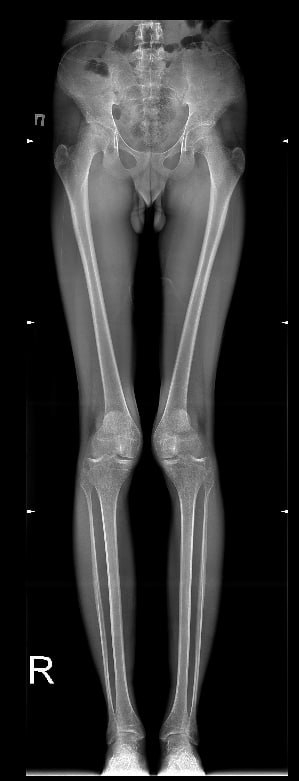

В этом треде обсуждаем разрушение суставов. Коленей, тазобедренных, плечевых, локтевых. Любых.

Остеоартроз – заболевание суставов, характеризующееся дегенерацией (разрушением) их хрящевой ткани и других структур, образующих сочленение – субхондральных (подхрящевых) частей кости, капсулы, синовиальной оболочки, связок, мышц. Хрящевая ткань, покрывающая суставные поверхности, истончается и разрушается, уменьшается количество синовиальной жидкости – возникают боль, отечность, деформация сустава. Выздороветь от этой патологии нельзя – восстановить разрушенный хрящ невозможно. Своевременная верификация болезни и адекватное лечение помогут замедлить прогрессирование патологического процесса и надолго сохранят качество жизни пациента.

Данные по артрозу разнятся. Чаще всего им страдают женщины, но у мужчин он появляется раньше. До 45 лет у 2-3%, что скорее генетическое, после 45 лет у 30%, после 60 лет у 60-80%.

В молодом возрасте артроз может возникать в следствии травм.